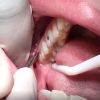

Kısmen gömülü 20 yaş dişleri, ağız ortamına tamamen çıkamamış, üzerleri kısmen diş eti ile örtülü 20 yaş dişleridir. Üzerlerini kısmen örten diş eti nedeni ile gıda birikimine ve bakteri plağı oluşumuna uygun bir zemin hazırlayabilmektedirler. Bu dişlerin, diş dizisinin en arka bölgesinde yer almaları hijyen gerekliliklerinin sağlanmasını da zorlaştırmaktadır.

Tüm bu durum bir arada düşünüldüğünde bu dişler; çürüme veya üzerlerini örten diş etinde perikoronitis olarak adlandırılan ve genellikle tekrarlayan bir enfeksiyon tablosu olarak karşımıza çıkan bir klinik durum yaratma eğilimi göstermektedirler.

Bu enfeksiyon durumu; basit lokal bir enfeksiyon tablosu olarak kalabileceği gibi, tedavi edilmezse ilerleyen dönemlerde hayati tehlike oluşturabilecek baş boyun apselerine neden olabilmektedir. Bu sebeplerden ötürü çenelerimizde tamamen sürmeyi başaramamış 20 yaş dişlerinin gerekli klinik ve radyolojik muayene sonrasında uygun cerrahi yöntemler ile çekilmesi gerekmektedir.